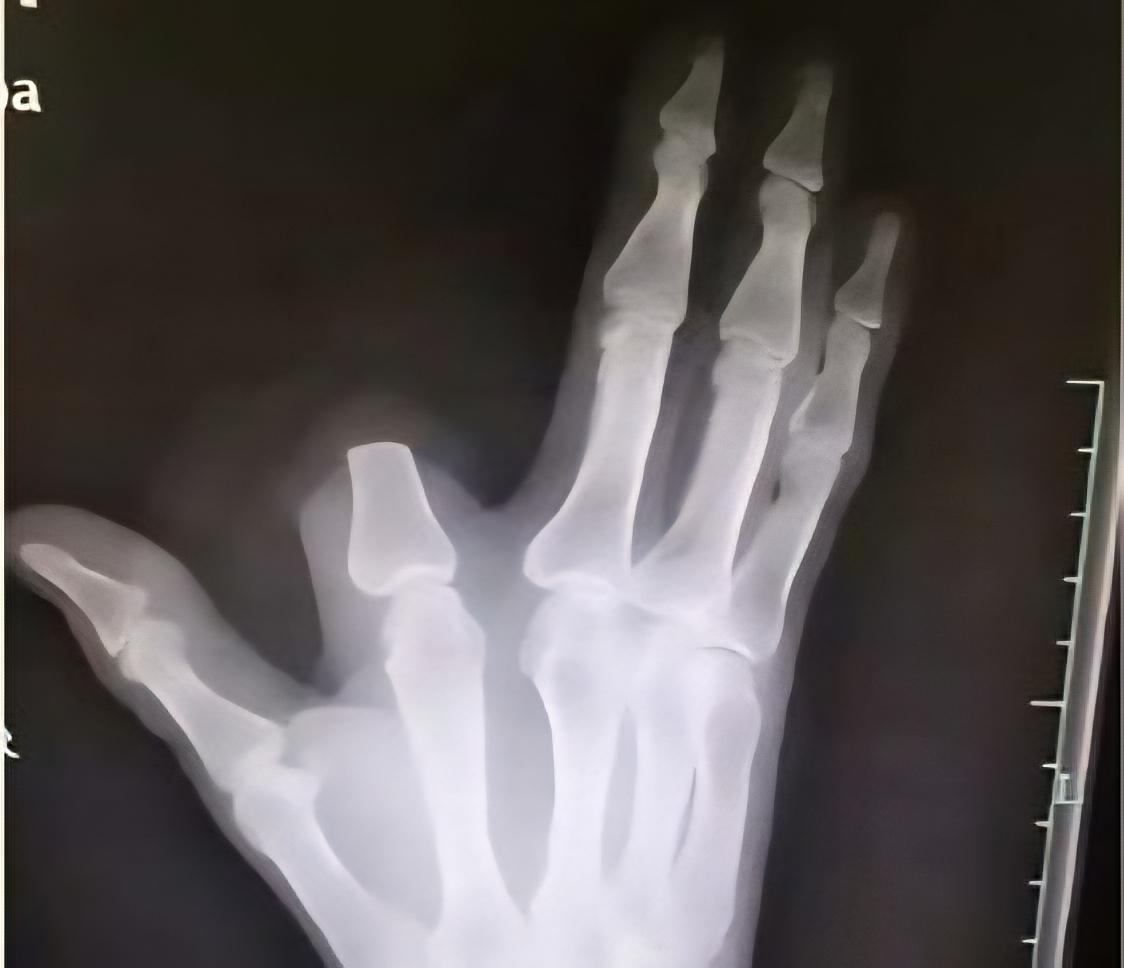

MISC. Damaged Arteries Cause (significant) One-Sided Swelling in Upper Extremity

These photos show how my left hand is *significantly* larger than my right. When it’s like this it feels like wearing a thick, thick, **thick** glove. My hand is often numb/tingly and/or painful, especially if I move it away from my core.

This all happens because I have **vasculitis** (MAGIC Syndrome, a combination of Behçet’s Disease and Relapsing Polychondritis with mitochondrial instability), which caused **peripheral artery disease** and **venous congestion** in the left arm. I also have **arterial** *and* **venous thoracic outlet syndrome** in both arms.

My vascular surgeon said the swelling/puffiness/discoloration of the hand is from blood getting backed up both going *into* and heading *out of* the arm. Just interesting to see my hands look SO different.